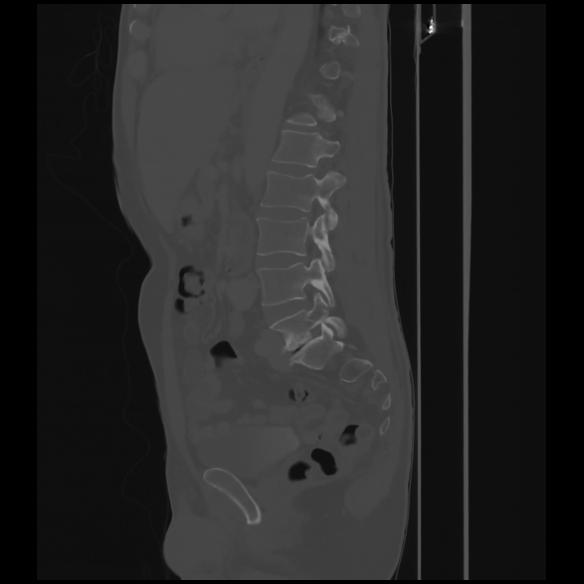

7 CUERPO,CE,Sagittal,3.000,CUERPO,Sagittal,